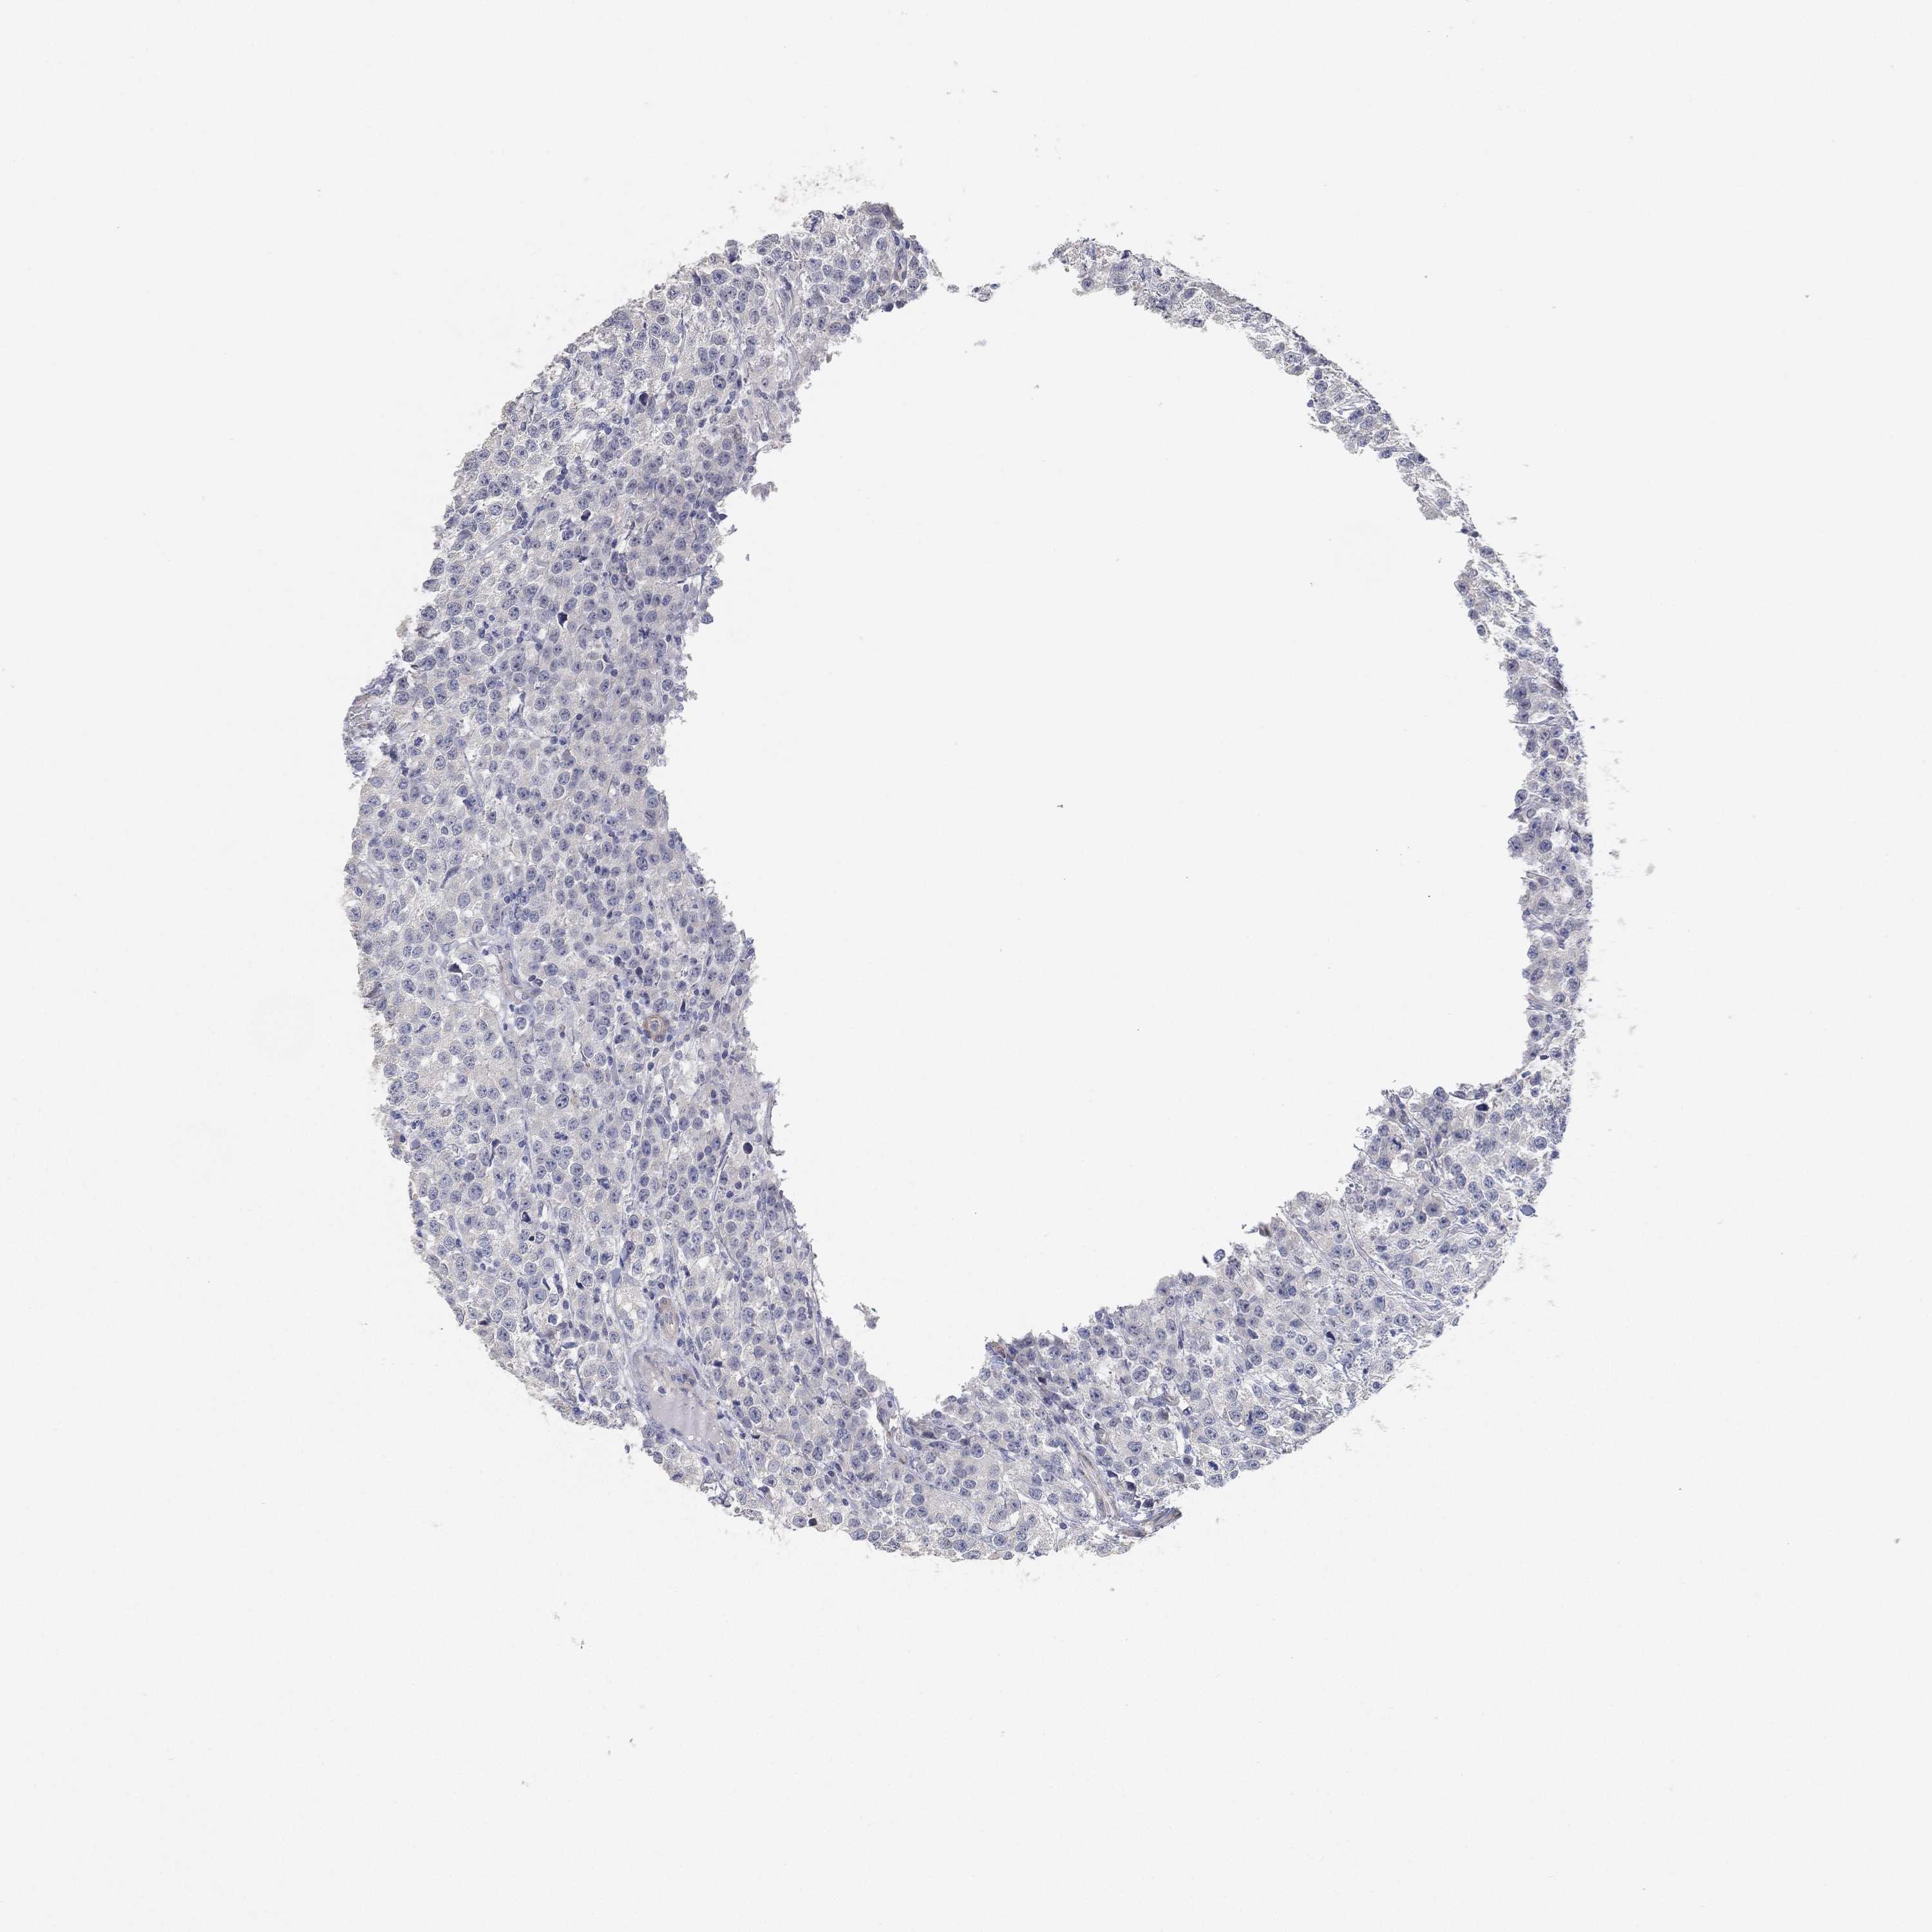

TESTIS CANCER - Protein expressioni

A mouse-over function shows sample information and annotation data. Click on an image to view it in a full screen mode. Samples can be filtered based on level of antibody staining by selecting one or several of the following categories: high, medium, low and not detected. The assay and annotation is described here.

Note that samples used for immunohistochemistry by the Human Protein Atlas do not correspond to samples in the TCGA dataset.

Antibody stainingi

Antibody staining in the annotated cell types in the current human tissue is reported as not detected, low, medium, or high, based on conventional immunohistochemistry profiling in selected tissues. This score is based on the combination of the staining intensity and fraction of stained cells.

Each image is clickable and will lead to virtual microscopy that enables deeper exploration of all samples and also displays staining intensity scores, fraction scores and subcellular localization as well as patient and tissue information for each sample.

Antibody HPA007326

Antibody HPA026088

Seminoma, NOS

Carcinoma, Embryonal, NOS